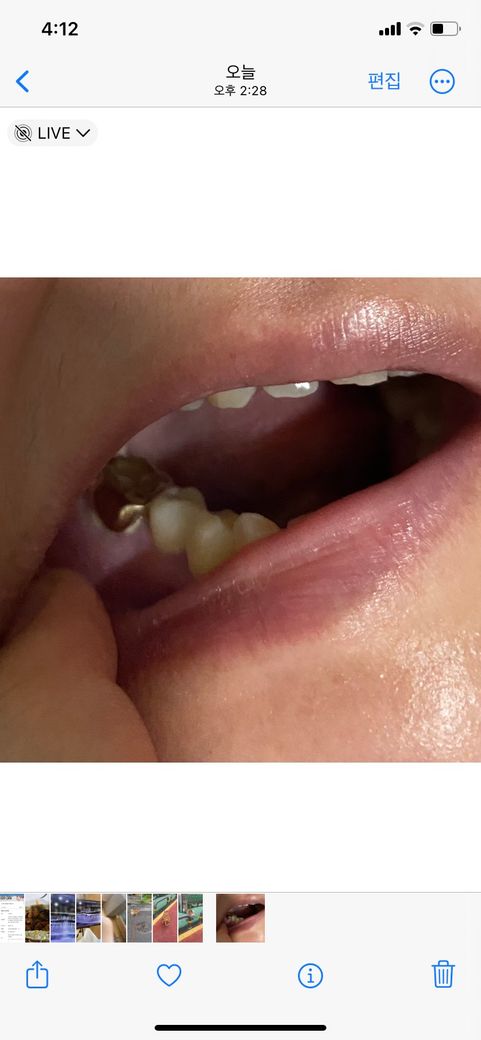

첫번째 사진 같이 크라운 한 치아에 흰고름이 나오는 증상으로 어제 잇몸치료를 했습니다(염증 긁어내는 치료)

근데 잇몸치료 후에도 사진 정도까진 아니고

덜 나오긴 하는데 여전히

쪼금씩 나오는데 이거 잇몸상처가 아무는 기간동안(2주동안 상처가 아문다고 하더군요) 나아지는 것인가요?

• 2번 째 사진